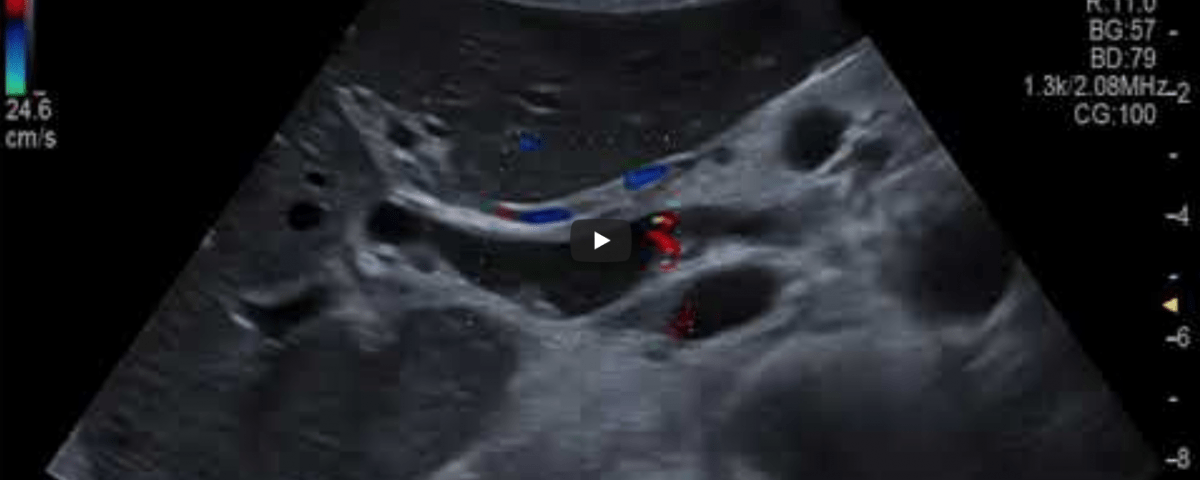

Student Image Challenge #110

Case:   The 55-year-old female patient was admitted as an emergency case with severe, wave-like pain in the upper right abdomen that had been ongoing for several hours, radiating to the right shoulder and accompanied by nausea, vomiting, and the onset of yellowish discoloration of the sclera.

What is the diagnosis?